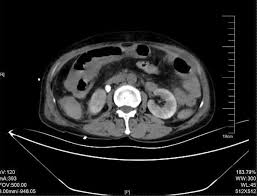

Bowel perforation occurs when a hole develops in the wall of the intestine. This can happen due to a variety of factors, including trauma, infection, and certain medical conditions. In the case of ESWL, bowel perforation is thought to be caused by the shock waves themselves.

The shock waves used in ESWL are powerful enough to break up kidney stones, but they can also damage nearby tissues. If the shock waves are focused on the wrong area, they could potentially cause a bowel perforation. However, this is a very rare occurrence.

ESWL is a generally safe procedure, and the risk of bowel perforation is very low. Doctors are very careful to avoid targeting the bowel during the procedure. They use imaging techniques to ensure that the shock waves are focused on the kidney stones.